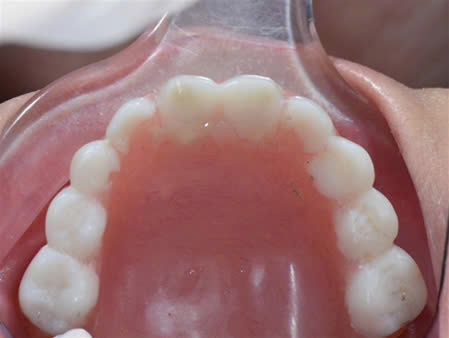

Đặc biệt biểu hiện ở răng:

Tùy mức độ từ nhẹ đến nặng của bệnh mà có biểu hiện ở răng từ thiếu một vài răng đến thiếu nhiều răng đến không có răng.

Trường hợp thiếu răng: răng trong miệng thường bị dị dạng, có dạng hình nón hoặc hình chóp.

Do tình trạng giảm tiết nước bọt trong miệng nên các trường hợp khiếm khuyết men răng và sâu răng xảy ra thường xuyên.

Hình 2: Ảnh chụp trong miệng